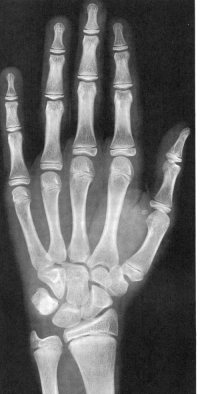

Sexo Masculino

8 anos